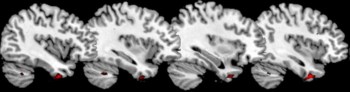

A vermelho são as áreas dos pólos temporais com menos massa cinzenta nos psicopatas

As zonas a vermelho são áreas do córtex pré-frontal com menos massa cinzenta do psicopata

Os cientistas utilizaram a ressonância magnética para obter imagens do cérebro de 44 homens adultos que tinham cometido homicídios, violações, tentativas de homicídio ou causado ferimentos corporais graves a terceiros. Desses, 17 correspondiam ao perfil do psicopata, mas não os restantes 27. Também estudaram os cérebros de 22 pessoas não criminosas. E quando compararam as imagens, viram que os psicopatas, e só eles, apresentavam volumes de matéria cinzenta significativamente reduzidos em duas áreas: na região anterior rostral do córtex pré-frontal e nos pólos temporais. Estas duas áreas são importantes na percepção das emoções e das intenções alheias e são activadas quando pensamos em comportamentos morais, explica o mesmo comunicado. E as lesões nessas áreas têm sido associadas à falta de empatia, de medo, de angústia e de sentimentos de culpa e de vergonha.